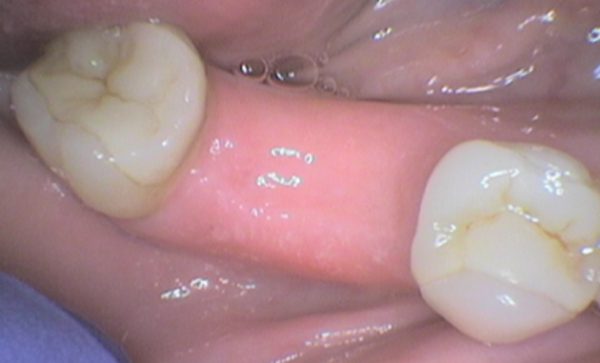

Case 6